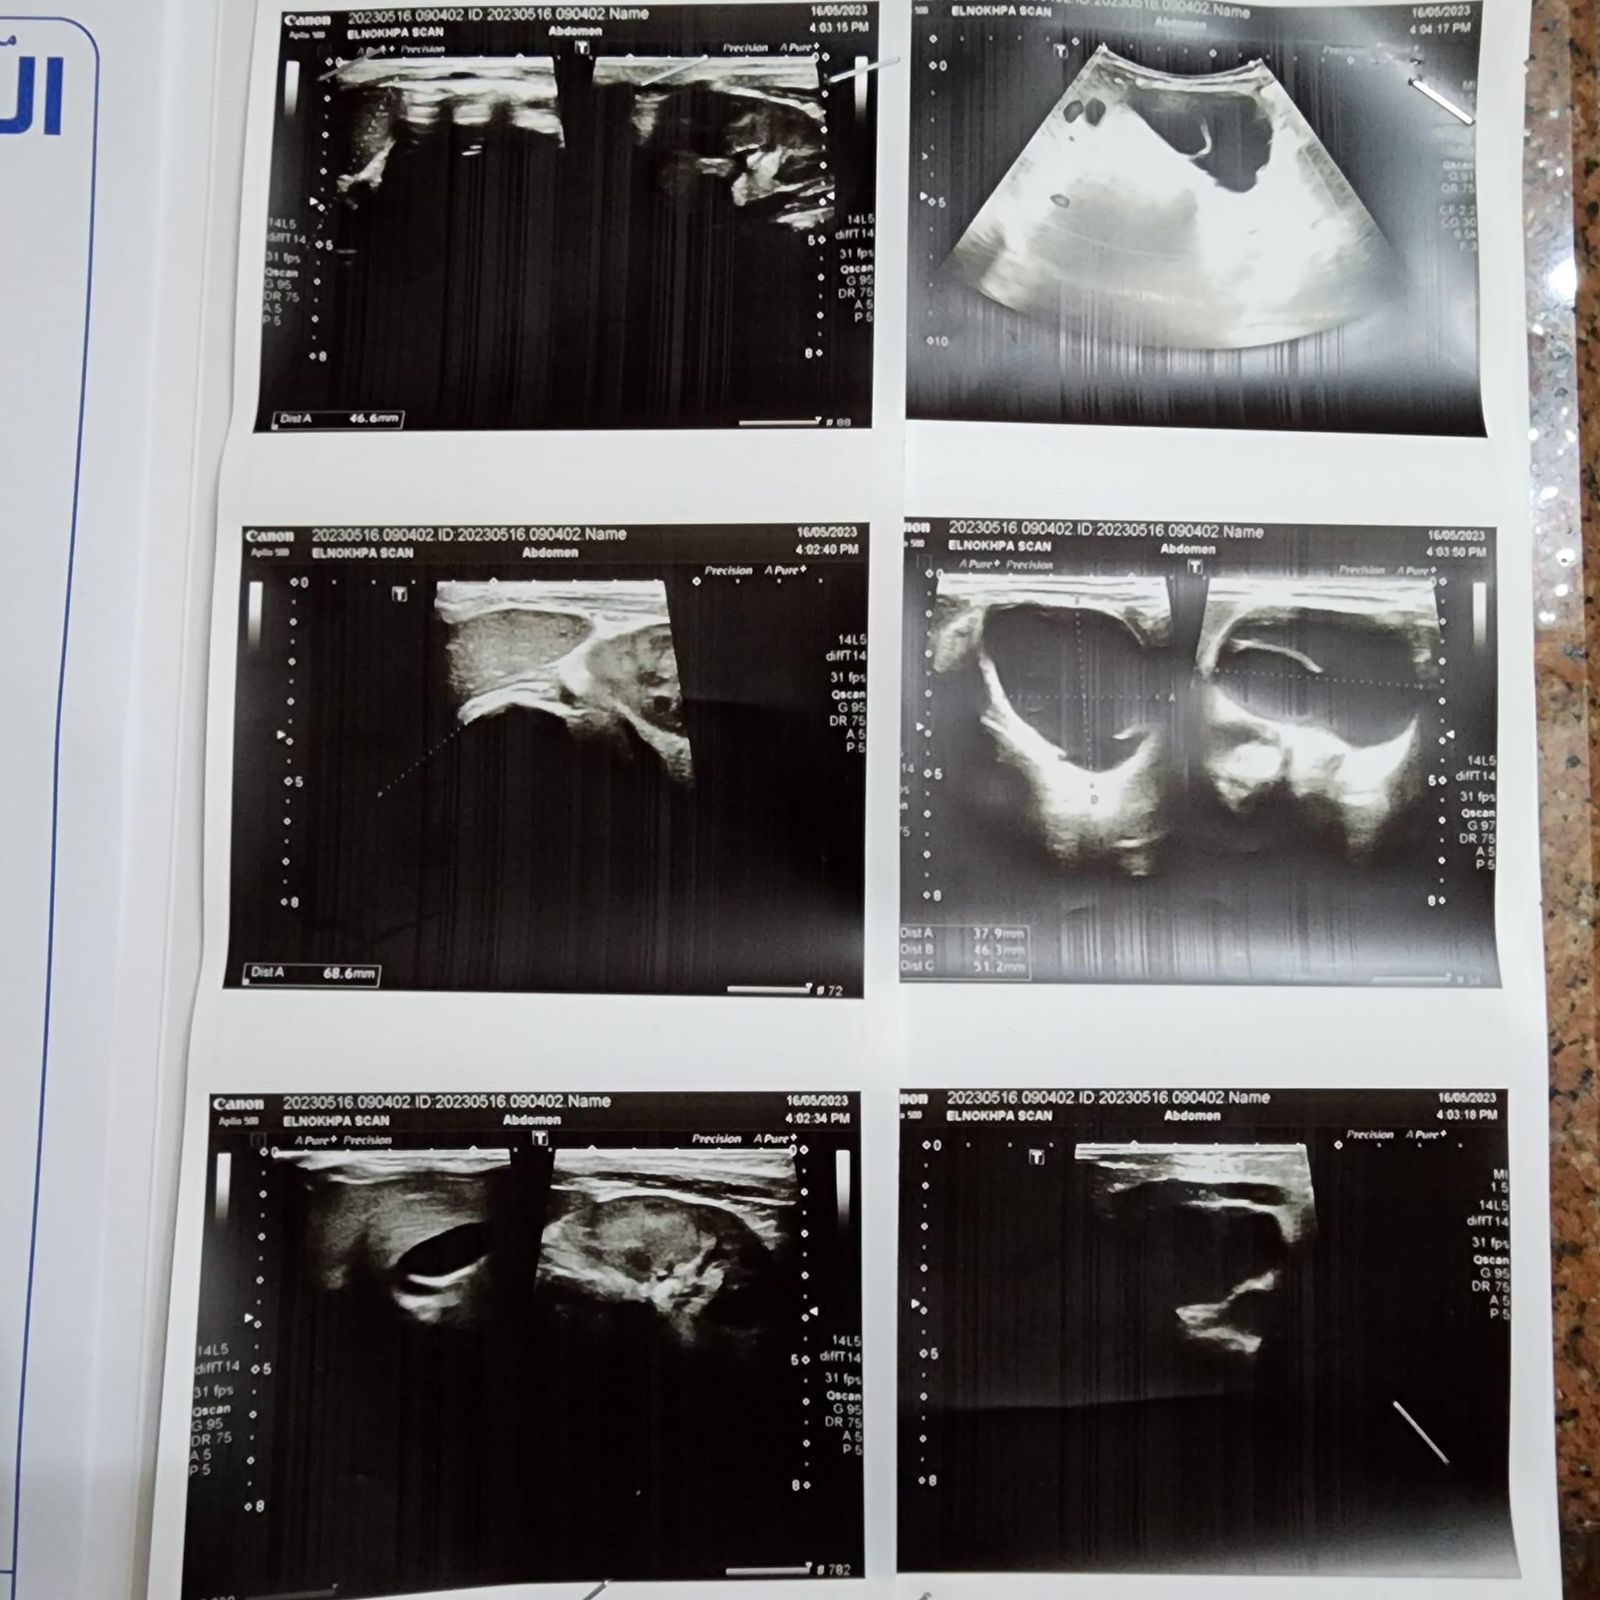

وأوضحت والدة الطفلة نورين، أنها اكتشفت الورم من خلال ظهور بعض الأعراض على الطفلة، ومنها التقيؤ المستمر، ومن خلال إجراء بعض الفحوصات الطبية، تبين أن الطفلة تعاني من ورم نادر في البطن بحجم 13 سم في الجانب الأيمن من الجسم بالكامل، بالإضافة إلى أنه ضاغط على الكلى والشريان الأورطي وباقي أجهزة الجهاز الهضمي.

وطالبت بتسريع دخول ابنتها مستشفى سرطان الأطفال، قائلة: الدكاترة شخصوا حالتها بورم سرطاني نادر، وهو حالة تراتوما، وضاغط على أجهزة الجسم غلط، احنا محتاجين تسريع موعد العملية لأن الورم بيكبر، ومع سن بنتي العملية صعبة وخطيرة.